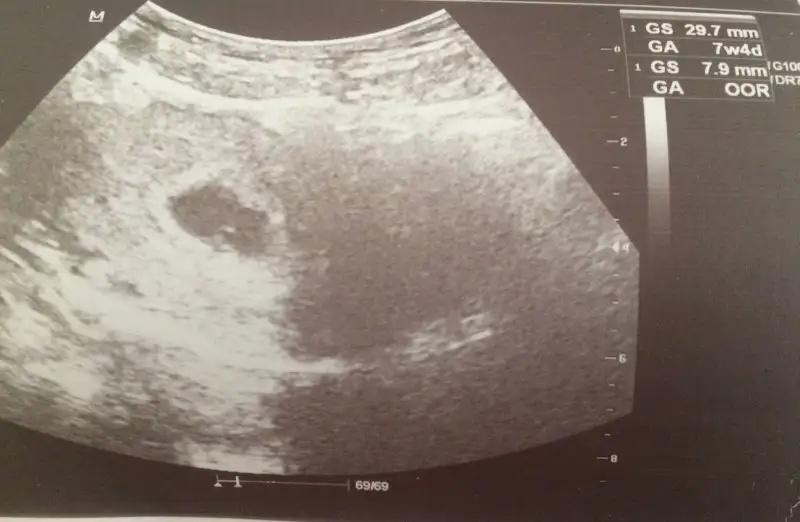

Doktordan geldik. Keseyi gördük çok şükür herşey yolunda. D ve B12 değerlerim çok düşük onun için de takviye verdi.

Canm birde ben sata Gore 5+5 haftalk gözüküyorm 8mm kese normal mi ?? Sanırm gec catlams yumurtam bu ay S Sempatikhatun20

Himm o zaman daha 1 aylk yok bebis :) sağol canm sen gordun mu keseyi fotu attinmi?CNm satı boşver ultrasona göre gitçez artık